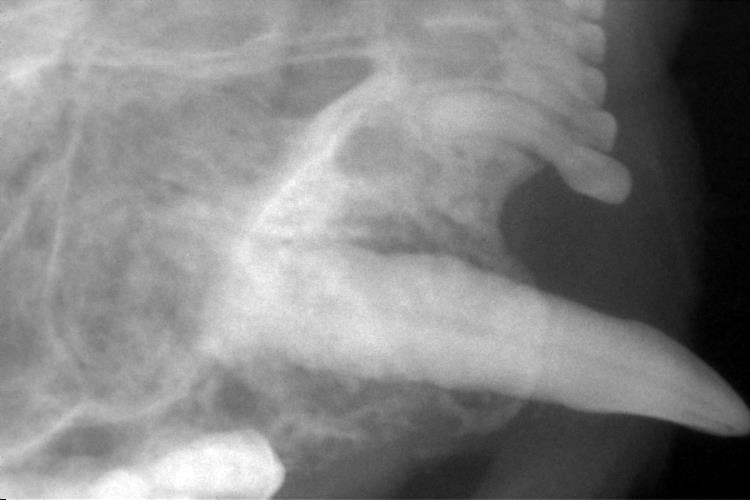

歯科レントゲン検査

右下顎臼歯です。

ぐらつきがひどく、レントゲンでも歯の周りが黒く抜け、歯槽骨が吸収されているのがわかります。

歯周ポケットが深かった右上顎犬歯も歯槽骨の吸収が見られました(青色の部分が吸収され黒く抜けています)